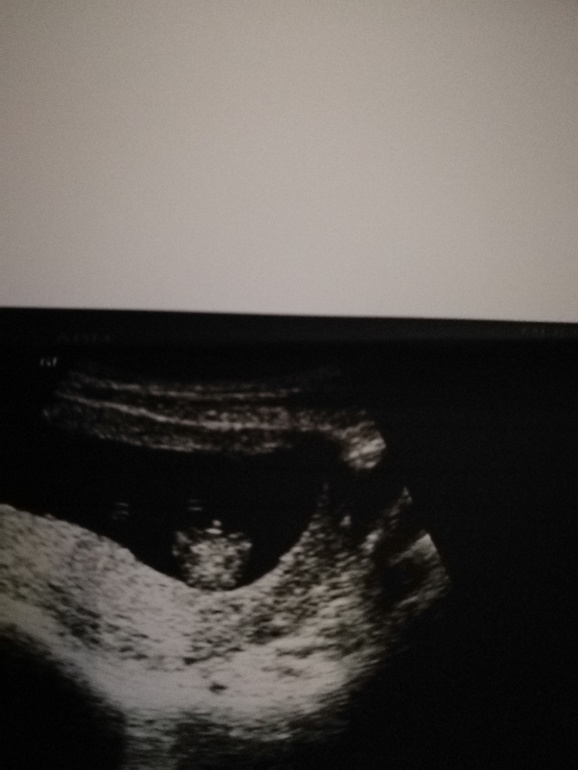

Из-за поясницы сделала узи. Поставили лёгкий тонус, о как.

Снова сделала узи.

Снова другой врач увидел мальчика, но я, в принципе и не сомневаюсь уже.

Сам малыш смешной, крутился и сосал свой пальчик) а это наш писюн) новый ракурс))

Спасибо))))) сказали, фаберже пока не видать, но вот писюн очень хорош) клитора такими не бывают)